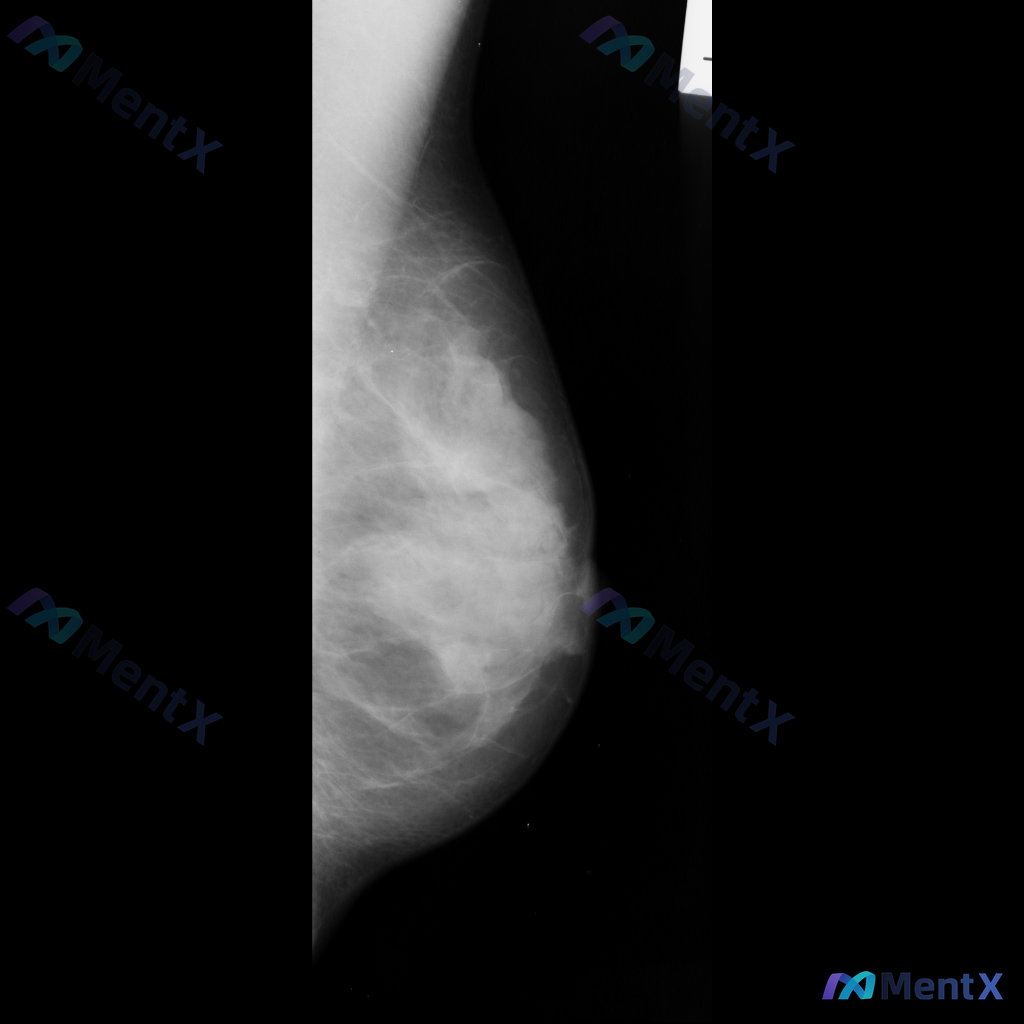

整理到一张乳腺钼靶影像的读片讨论资料: 影像显示右乳腺局部区域存在一不规则高密度肿块,伴有毛刺状边缘及局灶性结构扭曲。 想先跟大家讨论一下:单看这组特征,你首先会往哪个方向考虑?后续又会建议如何处理?

整理到一张乳腺钼靶影像的分析资料,大家可以先基于现有信息讨论一下。 基本影像学表现 - 可见形态不规则的致密区域,伴有结构扭曲和模糊边缘 - 背景乳腺腺体呈 BI-RADS B/C 型(致密性增加) 目前从影像上看,存在几种可能的方向,想听听大家的第一判断:单看这组影像学表现,你会先考虑哪一种异常方...

整理到一张乳腺钼靶影像的异常表现,分享给大家讨论: 一侧乳腺可见不规则形高密度致密影,伴有明显的结构扭曲和局部腺体结构紊乱。 单看这组影像描述,大家会优先往哪种方向考虑?后续如果要进一步明确,你觉得哪些步骤比较关键?

整理了一份乳腺钼靶影像病例,想和大家交流下判断思路。 影像表现: - 乳腺内可见不规则高密度肿块 - 肿块边缘呈毛刺状 - 伴有周围乳腺结构的扭曲和牵拉 目前可以考虑的方向有几个,想先问问大家:单看这份影像描述,你第一反应会更倾向哪一种情况?